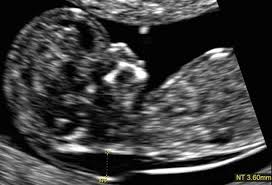

The ultrasound itself will take about 20 minutes to perform. This test measures the size of the clear tissue, called the nuchal translucency, at the back of your. It's often used during pregnancy to check the health of an unborn baby. The nuchal folds are on the back of the fetus's neck, and measuring the thickness of the nuchal folds—an indicator of how much fluid there is inside the folds—can provide information on possible issues with the fetus, including. When the nt is greater than 3.5 mm, there is a 1 in 5 chance of a chromosome abnormality such as turner or down syndrome, or trisomy 18. A look at what your scans will involve. The nuchal translucency screening, or nt, is a prenatal ultrasound test that can help to determine the fetus's likelihood of having down syndrome or some other chromosome abnormality. Before you arrive for your appointment we strongly encourage you to decide which screening test you would like to use to assess the results of your ultrasound.

Among the many terms you will learn and become familiar with is a nuchal scan. Or when your baby measures between 45mm and 84mm, crown to rump. At times, the nuchal translucency test may add on ultrasound markers, such as measuring a baby's. Normally she does it with transabdominal approach. Nuchal translucency (nt) normal range pregnancy is a time when people tend to learn a lot of new terminology. First trimester screening includes an ultrasound exam to measure the size of the clear space in the tissue at the back of a baby's neck (nuchal translucency). This page explains what the acronym nt means. Nuchal translucency (nt) measures an area of fluid at the back of a baby's neck. A nuchal translucency (nt) ultrasound measures the fluid at the back of a baby's neck between 11 and 14 weeks of pregnancy. Nuchal translucency ultrasound alone can also provide this risk assessment, but it is not as accurate as combined first trimester screening. The person performing the nt scan may also ask you to drink a glass of water before you begin. Before you arrive for your appointment we strongly encourage you to decide which screening test you would like to use to assess the results of your ultrasound. In malaysia, the overall rate of incidence for down syndrome is 1 in 800 births.

Additional tests should be ordered by an ob or genetic counselor for confirmation. The amount of fluid is measured during an nt ultrasound scan: Between 11 weeks and 13 weeks plus six days of pregnancy. Nt is an acronym that stands for nice try, which is typically seen when gaming online. The fourth dimension is time, because it is a video and not just a still image. Among the many terms you will learn and become familiar with is a nuchal scan. The nuchal folds are on the back of the fetus's neck, and measuring the thickness of the nuchal folds—an indicator of how much fluid there is inside the folds—can provide information on possible issues with the fetus, including. Or when your baby measures between 45mm and 84mm, crown to rump.

It helps doctors determine if a baby is statistically more likely to have a chromosomal abnormality. In malaysia, the overall rate of incidence for down syndrome is 1 in 800 births. The amount of fluid is measured during an nt ultrasound scan: What do ultrasound abbreviations and initials mean? Measuring this thickness helps assess the risk for down syndrome and other genetic problems in the baby. A nuchal translucency (nt) ultrasound measures the fluid at the back of a baby's neck between 11 and 14 weeks of pregnancy. Nuchal translucency (nt) measures an area of fluid at the back of a baby's neck. Nuchal translucency ultrasound alone can also provide this risk assessment, but it is not as accurate as combined first trimester screening. It should not be confused with the nuchal fold, which is seen in the second trimester. It is same as normal sound in its physical properties, but humans cannot hear it. A normal amount of fluid in the back of the neck during ultrasound means it is very unlikely your baby has down syndrome or another genetic. A nuchal translucency (nt) test uses abdominal ultrasound to measure the nuchal fold thickness of the fetus. The letters that are next to the numbers on an ultrasound represent different measurements of the baby.

The ultrasound nt scan or nuchal translucency scan is an ultrasound to measure the amount of fluid that has been collected in the back of the neck of the fetus. A nuchal translucency (nt) ultrasound measures the fluid at the back of a baby's neck between 11 and 14 weeks of pregnancy. Nt focuses on a small, clear space at the back of a growing baby's neck called the nuchal fold. Major heart problems can also be detected using the nt prenatal test. Nuchal translucency (nt) normal range pregnancy is a time when people tend to learn a lot of new terminology. This is the ultrasound typically completed at the 12 week mark of pregnancy. The nuchal translucency screening, or nt, is a prenatal ultrasound test that can help to determine the fetus's likelihood of having down syndrome or some other chromosome abnormality. The amount of fluid is measured during an nt ultrasound scan: What do ultrasound abbreviations and initials mean? Nuchal translucency (nt) measurement nuchal translucensy (nt) is the clear space in the tissue of your developing baby's neck. Additional tests should be ordered by an ob or genetic counselor for confirmation. Ultrasound is a sound wave with a frequency higher than 20khz used to look at organs and structures inside the body. When there is more fluid than usual, it is called increased nuchal translucency or large